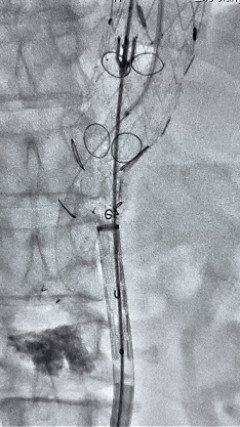

8. 从右侧股动脉入路送入腹主支架AB-24-12-110-S,近端重叠胸腹主动脉支架远端,调整好支架位置后释放。

9. 经左股动脉送入导丝导管,超选进腹主动脉支架短腿内,后沿导丝送入髂支,同理,右侧沿导丝送入髂支并释放,使用先健顺应性球囊后扩各支架连接处及支架近远端,最后通过预留导管向瘤腔注入人纤维蛋白粘合剂数支,造影显示分支通畅。

术后评价

G-Branch在本例手术中展现出对扭曲解剖结构的出色适应性,针对该患者严重扭曲的瘤颈,支架系统的优异柔顺性使其能够顺利通过复杂路径,完成内脏分支血管的重建。